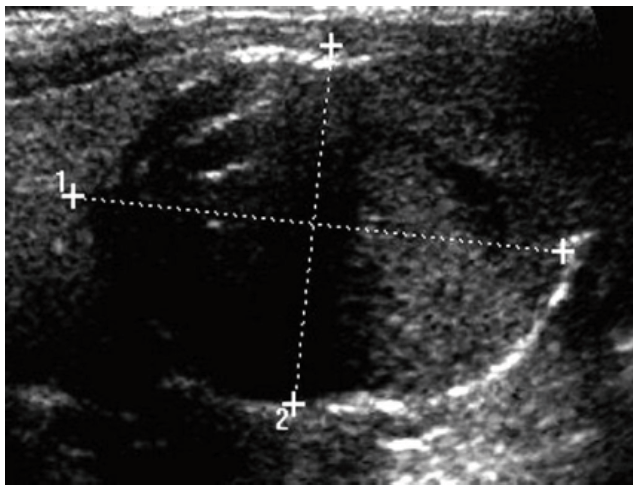

La ecografía tiroidea mostró agrandamiento global de la glándula, el lóbulo derecho medía 38 x 23 x 16 milímetros y el lóbulo izquierdo 51 x 26 x 22 milímetros. En el lóbulo izquierdo aumentado moderadamente de tamaño se encontró nódulo único, ligeramente hipoecogénico, heterogéneo, de aproximadamente 28 x 25 x 17 milímetros con aumento del flujo sanguíneo periférico, sin calcificaciones. No se observaron cambios del lóbulo derecho (figura 1). Los resultados de la gammagrafía con 99mTecnecio mostraron captación acentuada, difusa y homogénea en toda la glándula tiroides. El nódulo mostró captación central, elevada y focalizada correspondiente a nódulo hipercaptante (figura 2). Dadas las características del nódulo, la posibilidad de biopsia por aspiración con aguja fina fue descartada. En vista de los hallazgos clínicos, bioquímicos y de imágenes compatibles con una enfermedad de Graves asociada a un nódulo tiroideo izquierdo autónomo, la paciente fue diagnosticada con SML.